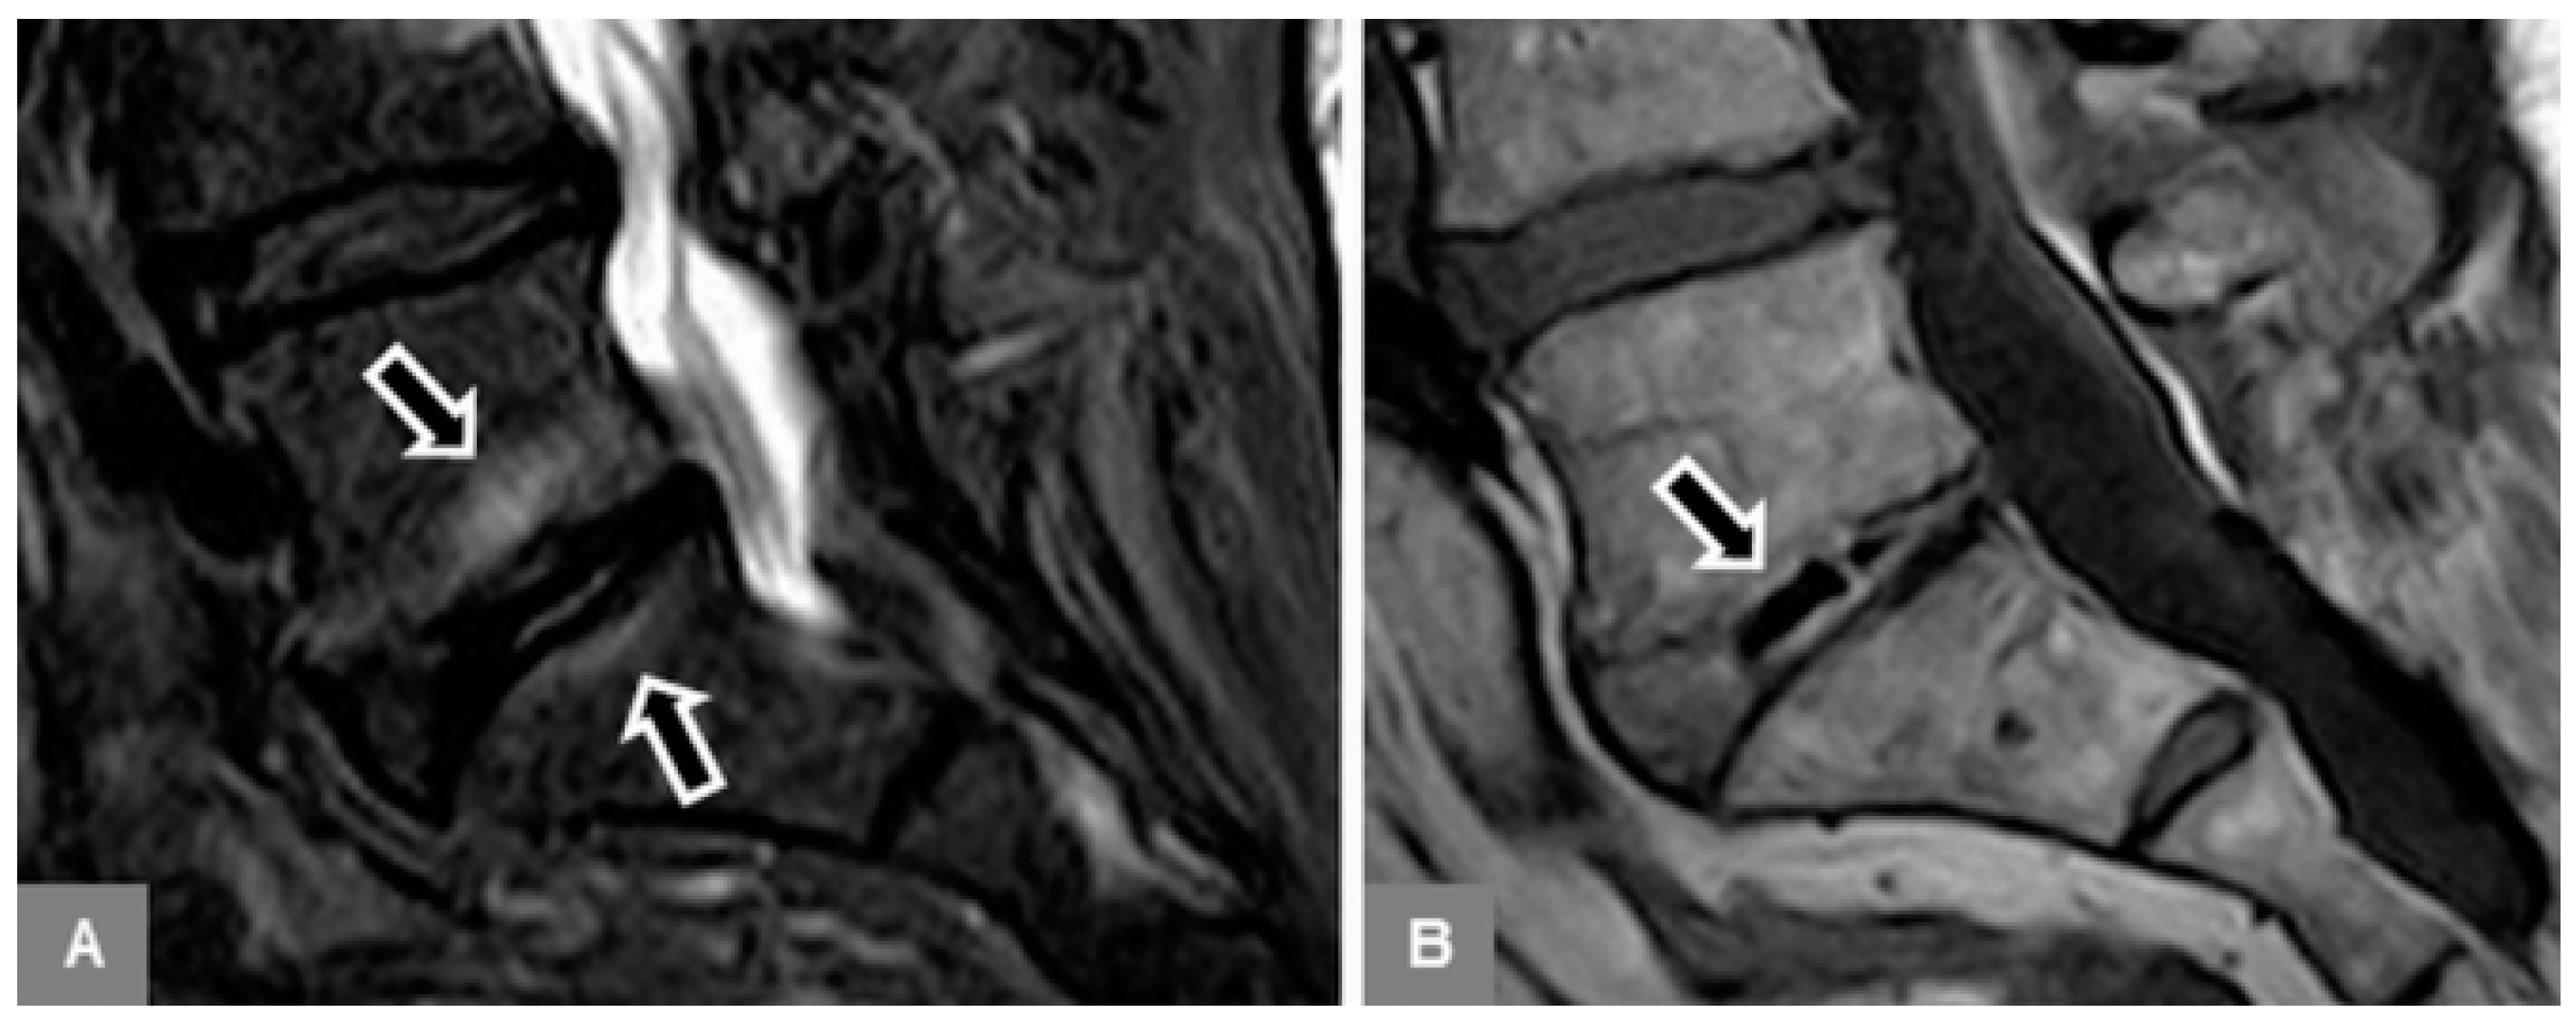

3.5. Appearance of the Intervertebral Disc

3.6. Modic Type 2 and 3 Endplate Changes